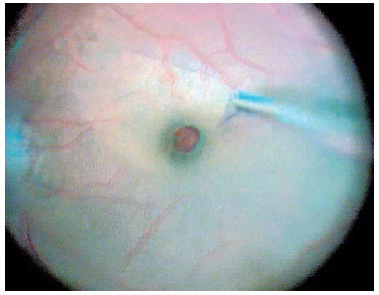

After the vitreous was completely removed, 0.3 mL of 0.05% BBG was flushed through the posterior pole using a 23-gauge soft-tip cannula, which was subsequently disconnected carefully from the infusion system to avoid injection directly into the hole (Figure 2). The BBG injected had a concentration of 0.5 mg/mL, osmolarity of 280 mOsm, density of 1.1, pH of 7.00, and an intense dark-blue color.

For macular surgery, a Machemer contact lens (Volk, Cleveland, OH, USA) was used, and the ILM was peeled using 23-gauge intraocular forceps. Peeling was initiated by grasping the ILM over the inferior macular region with the forceps or using a Finesse™ flex loop to create an ILM flap (Figure 3), and then it was extended in a circum ferential manner over the area, including the macula, without touching the retinal surface (Figure 4).